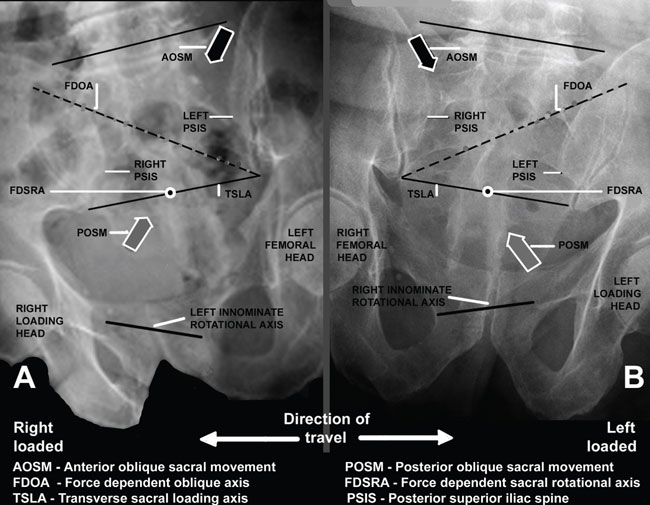

Sacral Movement on the Asymmetric Pelvis With Normal Ambulation

click

to enlarge

DonTigny ©

Oblique Sacral Movement on the Oblique Sacral Axis

The weight of the superincumbent trunk anterior to the oblique

sacral axis at S3 on the left causes

a sacral movement anteriorly at S1 on the left and posteriorly

at S3 on the right just as soon as the normal

axis on the symmetric pelvis begins to move into asymmetry. The

sacrotuberous ligament is helical and

allows this movement.

The longer the stride, the greater is the asymmetry, the greater

is the lateral sacral flexion and thus

the greater the sacral rotation on the oblique axis. An oblique

force couple is created from the posterior interosseous ligament

on the left to the sacrotuberous ligament on the right. The sacral

rotation drives trunk rotation toward the right (the side of loading),

precedes the loading and serves to decrease the impact loading.

Other than when loading and moving from recumbent to standing, normal sacral movement occurs during normal gait. When the pelvis moves obliquely to the line of travel in order to extend the length of the stride it moves from a position of symmetry into asymmetry. This position with one leg in the extreme forward position and the other in the extreme back position is called the extreme long straddle position. In this position the pelvic bone (innominate bone) on the side of the forward leg (the loading leg) rotates somewhat backward and downward on the sacrum while the pelvic bone on the side of the trailing leg rotates somewhat forward and upward. This movement on the sacrum causes the sacrum to flex laterally toward the side of loading. A force-dependent oblique axis of rotation is created. As the line of gravity is anterior to the sacral axis, the sacrum then moves on that oblique axis to drive counter rotation of the trunk on the loading side in order to decrease the loading forces and protect the head of the femur. This is a controlled instability and it can only occur with movement in the sacroiliac joint.